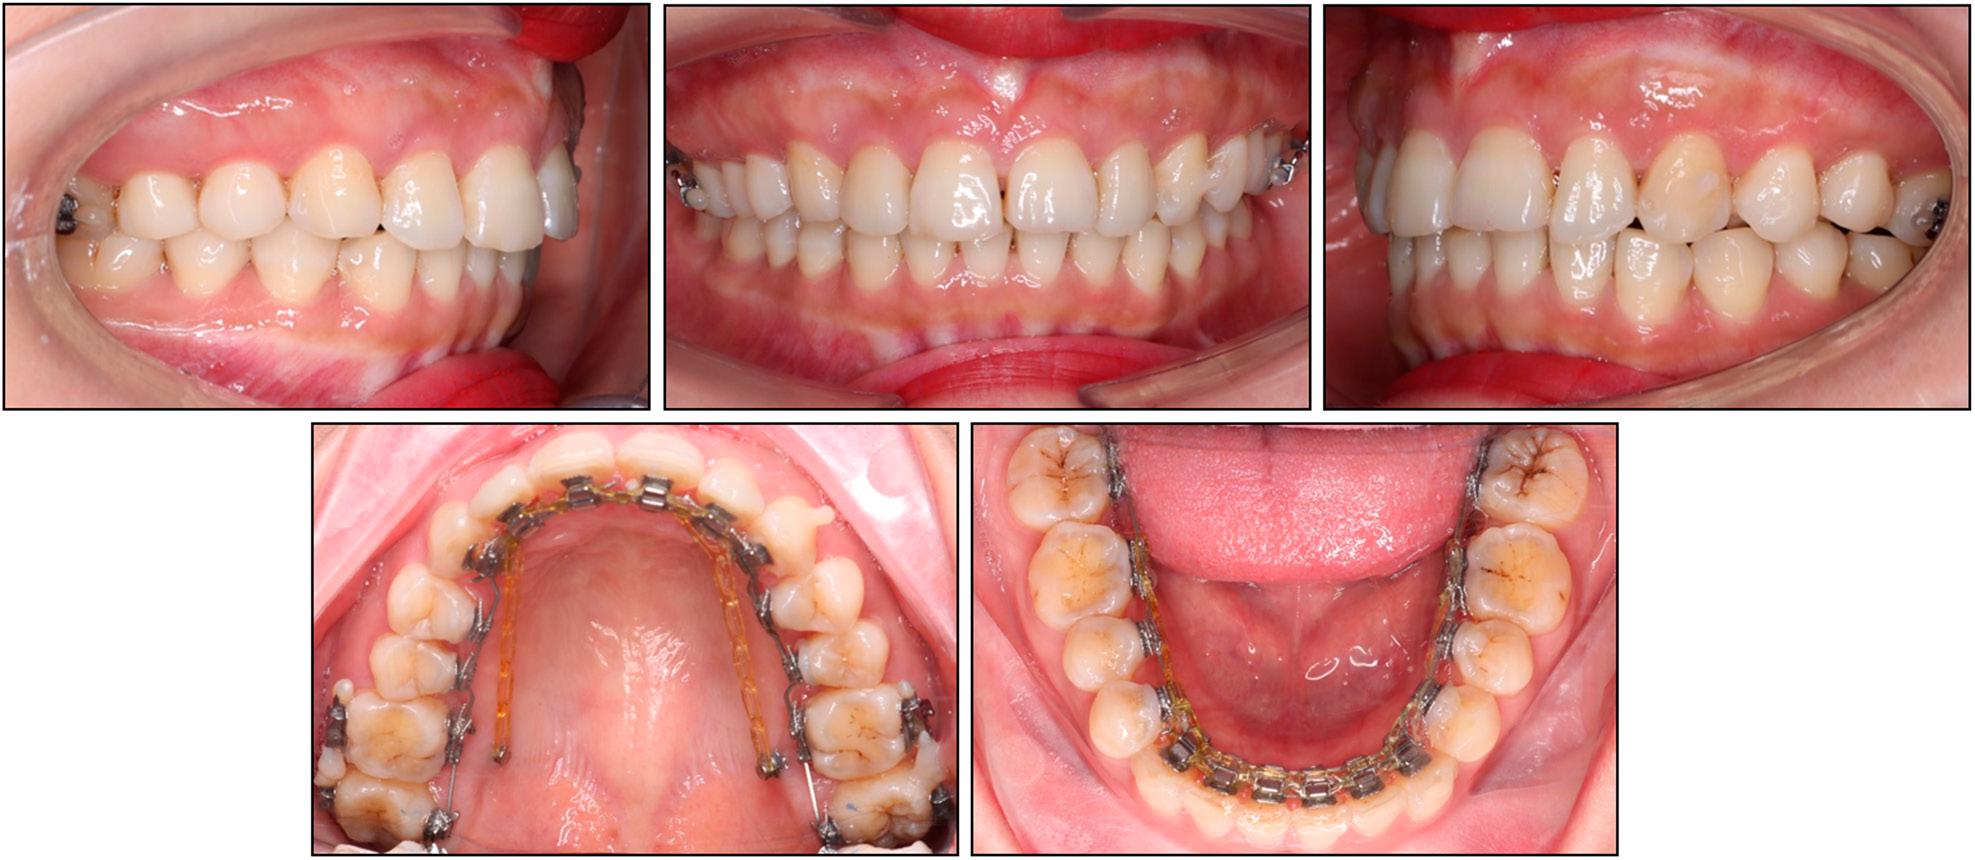

Cephalometric measurements

| Pretreatment | Posttreatment | |

|---|---|---|

| Skeletal | ||

| SNA (°) | 85.7 | 84.8 |

| SNB (°) | 79.6 | 80.1 |

| ANB (°) | 6.1 | 4.7 |

| FMA (°) | 20.0 | 20.5 |

| Dental | ||

| U1-SN (°) | 80.3 | 92.4 |

| U1-PP (°) | 89.2 | 101.1 |

| U1-NA (°) | -5.5 | 7.6 |

| U1-NA (mm) | -3.4 | -1.2 |

| IMPA (°) | 94.2 | 95.1 |

| L1-NB (°) | 22.1 | 22.7 |

| L1-NB (mm) | 2.8 | 3.1 |

| Interincisal angle (°) | 157.3 | 144.9 |

| Upper incisal display (mm) | 5.8 | 3.8 |

| Soft tissue | ||

| E-line/UL (mm) | -0.7 | -0.9 |

| E-line/LL (mm) | -1.2 | -1.2 |